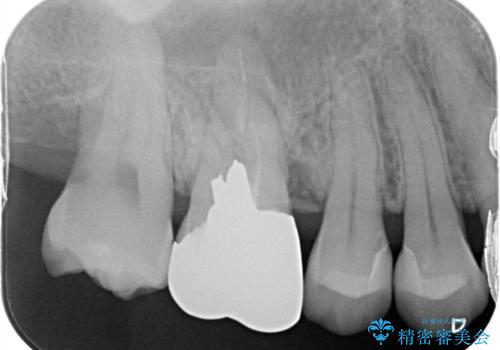

- 右上4、5の歯がしみるのを治したいという主訴で来院されました。精査の結果隣接面う蝕と診断し、適合がよく見ためも良いセラミックインレーでの治療を行いました。